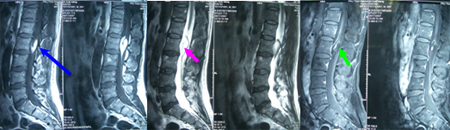

男性,56岁,左下肢无力8年,加重伴二便功能障碍1年。查体:双下肢肌萎缩,左下肢近端3级、远端0级,右下肢近端4级、远端3级,双侧膝腱、跟腱反射减弱,肛门外括约肌松弛,双侧病理征阴性。术前图片显示:肿瘤位于L2水平,呈蝌蚪状,短T1、长T2信号,压脂像脂肪明显抑制,未见强化表现。

术中见脂肪瘤性病变源于脊髓圆锥,终于末端终丝,脊髓有牵张、拴系表现。肿瘤下极部分切除后,剪断远端终丝。